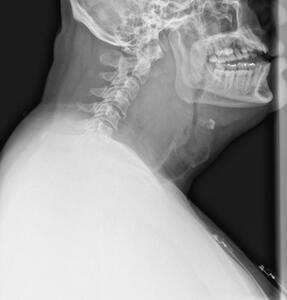

Upon insertion of the glidescope, vocal cord visualization was hindered by oropharyngeal excessive bleeding. Despite extensive suctioning, only the epiglottis was visible due to hematoma compression and soft tissue swelling obscuring distal anatomical structures. The patient’s SpO2 declined to the 80s despite spontaneous breathing, prompting two-person bag-mask ventilation with an oral airway insertion. A Grade III Cormack-Lehane classification was given, and subsequent successful glidescope intubation was made with a gum-elastic bougie (GEB) after SpO2 recovered to 100%. During this intubation, the GEB was blindly advanced below the epiglottis in the anterior direction, followed by the endotracheal (ET) tube passing over the GEB. Successful placement of the ET tube was confirmed by a CO2 color changer, auscultation, and chest x-ray. Propofol infusion at 50 mcgs/kg/min was started for sedation. A post-intubation CT scan showed evidence of compression from the nasopharynx to subglottic airways with the ET tube in good position above the carina (Figure 2). Midazolam 4 mg IV and fentanyl infusion at 50 mcg/hr was initiated for comfort. Once the airway was secured and the patient was hemodynamically stabilized, he was transferred to a higher-level care facility.